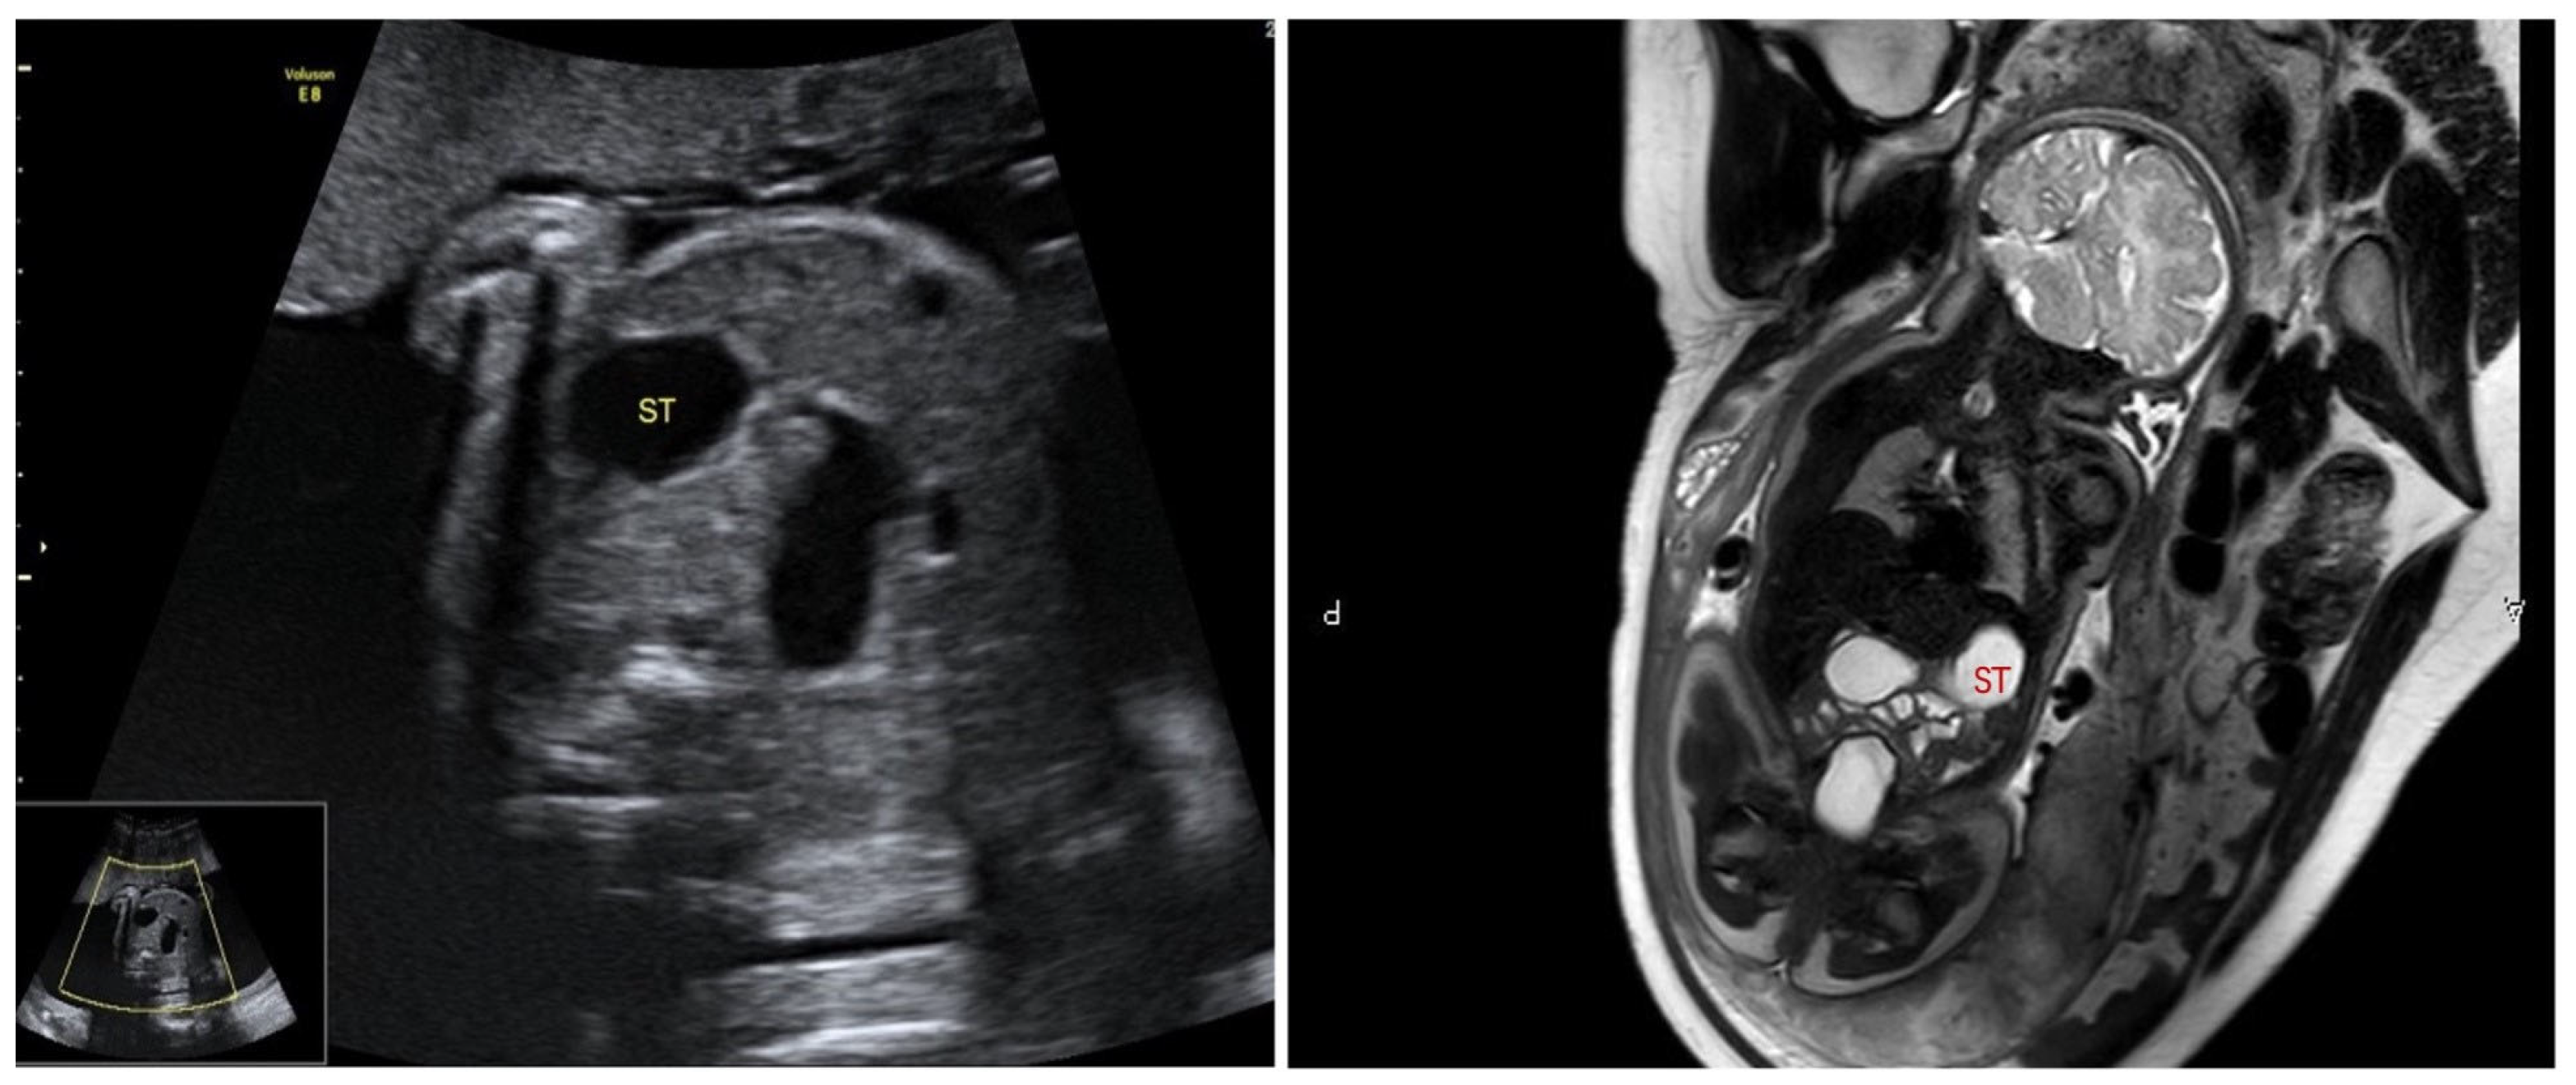

Based on the fetal ultrasound and MRI results, duodenal dilation was observed in 41 cases. In these cases, the dilated duodenum was connected to the gastric bubble, showing a typical sign like a double bubble (Figure 1). One hundred thirty-two ultrasound examinations were performed prenatally in these cases. GA at first time of diagnosis was 26.1 ± 4.5 weeks of gestation (range, 21+6–38+1 w). All these fetuses underwent an MRI examination prenatally and were confirmed with double-bubble sign. Subsequently, ultrasound was used to monitor the fetal development and changes in bowel dilatation. Each case received 3 ± 2 ultrasound examinations on average (1–9 examinations, mean = 3), with a continuous existence of double-bubble sign. Twenty-one cases were complicated with polyhydramnios. Forty newborns were confirmed to have congenital gastrointestinal malformations by surgical exploration in our department after birth, including twenty-one cases of annular pancreas (involving one case complicated with intestinal malrotation), sixteen cases of duodenal atresia (involving two cases complicated with intestinal malrotation), and three cases of atresia of the initial segment of the jejunum. Only one patient had no manifestations of intestinal obstruction after birth and was followed up for 1 year after discharge, with good growth and development. The accuracy of diagnosis of congenital duodenal obstruction using the fetal double-bubble sign was 97.6%.

A double-bubble sign is a radiological finding typically seen on abdominal X-rays, ultrasound, or fetal imaging. It refers to the presence of two gas-filled loops in the upper abdomen, representing the dilated stomach and proximal duodenum. This appearance suggests obstruction in the duodenum, often due to duodenal atresia or stenosis, but can also be caused by other congenital abnormalities such as annular pancreas or intestinal malrotation. The dilated stomach and duodenum create the characteristic “double-bubble” appearance on imaging. Many studies reported the fetal double-bubble sign is associated with duodenal atresia [1,2,7,13,15], but few studies found the double-bubble sign may be related to other malformations such as annular pancreas and atresia at the beginning of the jejunum. Furthermore, the correlation between GA at the first time of diagnosis and type of malformation needs to be explored. In this study, the accuracy rate of the prenatal diagnosis for gastrointestinal malformation by double-bubble sign was 97.6%, indicating a close relationship between duodenal obstruction and double-bubble sign. In this research, the average GA at first diagnosis of bubble-sign was 26.1 ± 4.5 weeks of gestation. Only one fetus with double-bubble sign discovered at 38 + 1 weeks of gestation firstly had no gastrointestinal malformations after birth. It is suggested that the double-bubble sign caused by pathological duodenal obstruction mostly appears in the second trimester. When the double-bubble sign first appears in the last trimester, the dilation of the bowel may occur as a concomitant phenomenon, alongside the progression of gestational weeks. Meanwhile, the proportion of polyhydramnios among these cases was as high as 51.2%, suggesting that polyhydramnios can be considered as an auxiliary indicator to predict gastrointestinal obstruction.

Figure 1. “Double-bubble” sign in ultrasound and MRI examination.